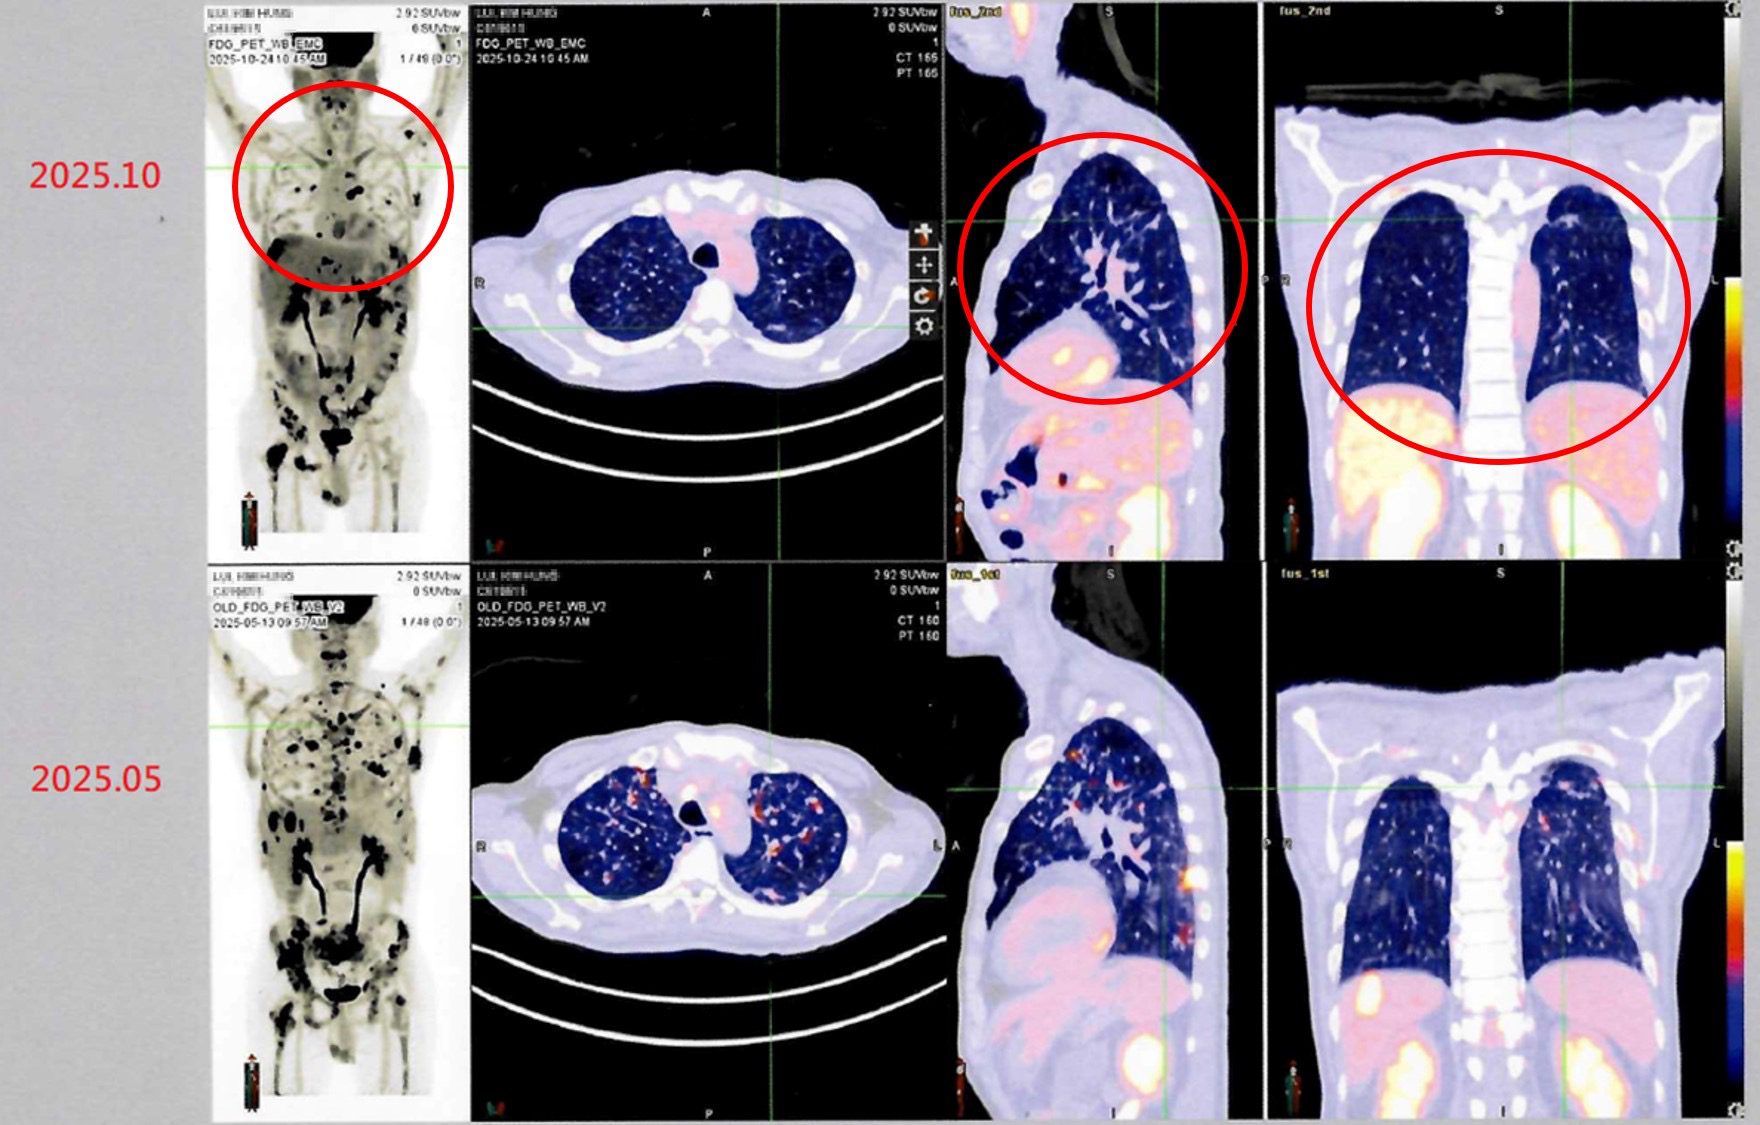

病人接受自體免疫細胞治療(DC-CIK)後,從治療前後影像資料對比(紅圈處),可發現癌細胞減少許多,顯示病情穩定。(照片由衛生福利部雙和醫院提供)